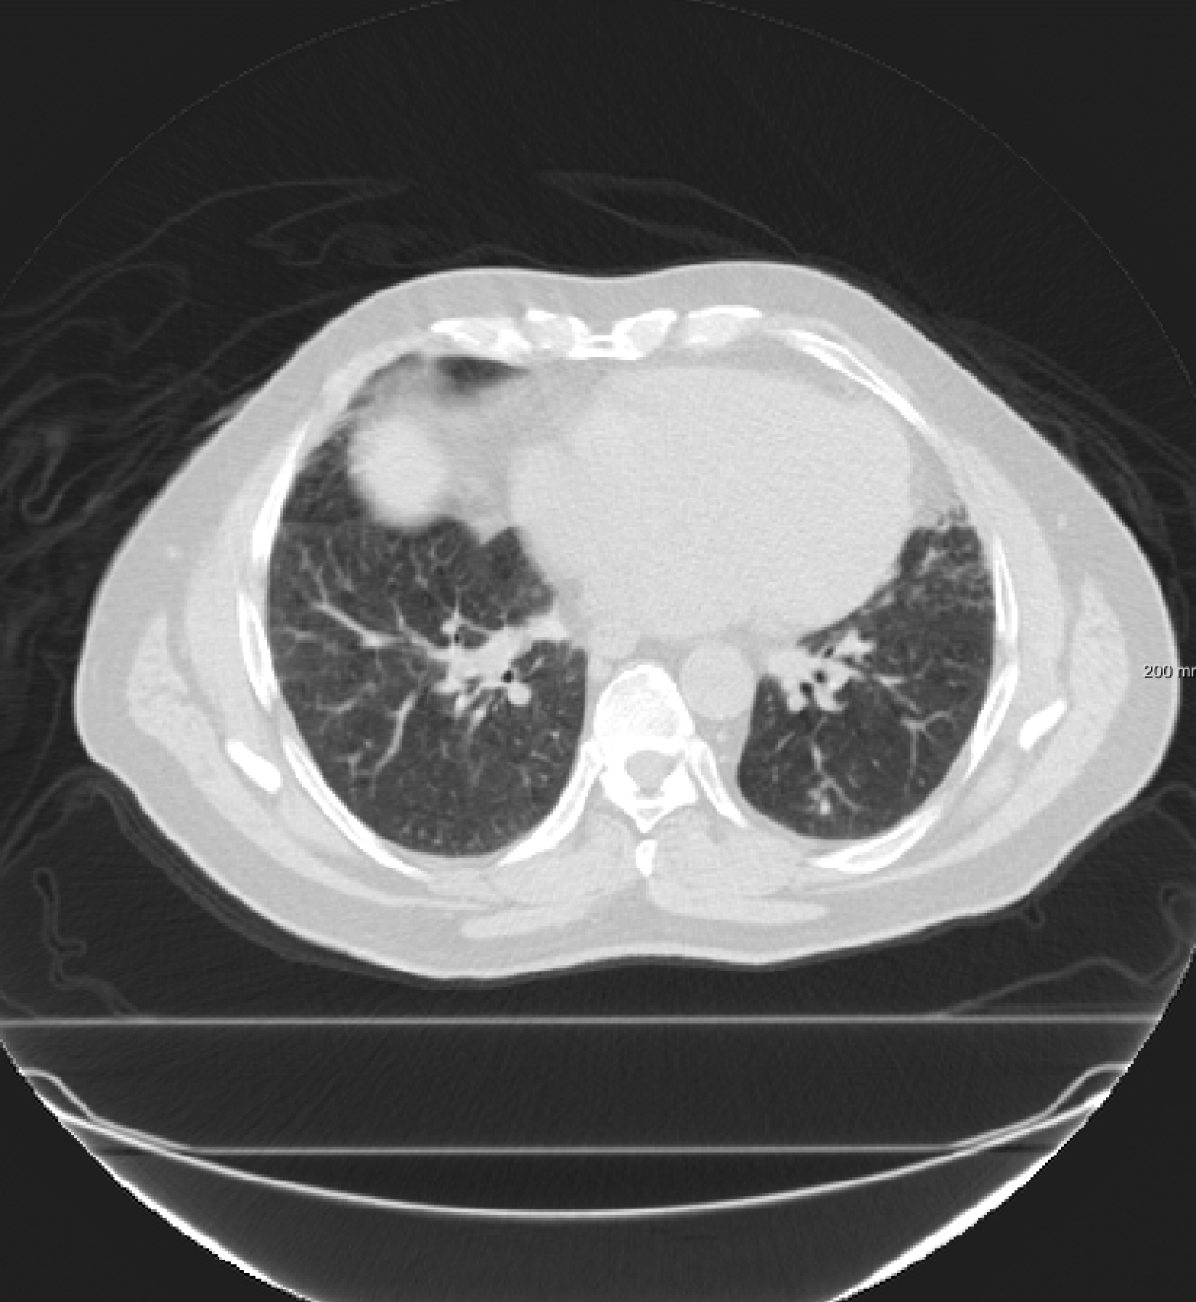

Three chest CT scan datasets are used in this study: The SPREAD (Stolk et al., 2007), the DIR-Lab-4DCT (Castillo et al., 2009) and the DIR-Lab-COPDgene dataset (Castillo et al., 2013).

In the SPREAD database, 21 pairs of 3D chest CT images are available with a baseline and a follow-up image in each pair. The follow-up images are taken after 30 months. Both images are acquired in the inhale phase. Patients in this study are aged between 49 and 78 years old. The size of the images is approximately with a mean voxel size of mm. About 100 well-distributed corresponding landmarks were previously selected (Staring et al., 2014) semi-automatically on distinctive locations (Murphy et al., 2011). Two cases (12 and 19) are excluded because of the high uncertainty in the landmarks annotation (Staring et al., 2014).

In the DIR-Lab-4DCT database ten cases are available. We use two phases of the available data: maximum inhalation and maximum exhalation. The size of the images is about with an average voxel size of mm.

For the SPREAD database, the TRE results with affine and B-spline registration are compared with three versions of RegNet trained using the category “S” (single frequency plus identity), “S+M” (single frequency and mixed frequency plus identity) and “S+M+R” (single frequency plus mixed frequency and respiratory motion plus identity). Since there is no respiratory motion in the SPREAD data, adding respiratory motion did not improve the performance of the registration. Adding mixed frequencies did not change the results considerably: there was a small improvement for the cases 1-11, and slightly larger TREs for the cases 13 to 21. The percentage of folding inside the lung masks for the RegNet trained using “S” is also available in Table III, which reports that the percentage of negative Jacobian are small in most cases, especially, when the TRE after affine registration is not very large. A Wilcoxon signed-rank test is performed between the elastix B-spline and other results. It can be seen that in most cases there is no significant difference between B-spline registration and RegNet trained using “S” or trained using “S+M”.